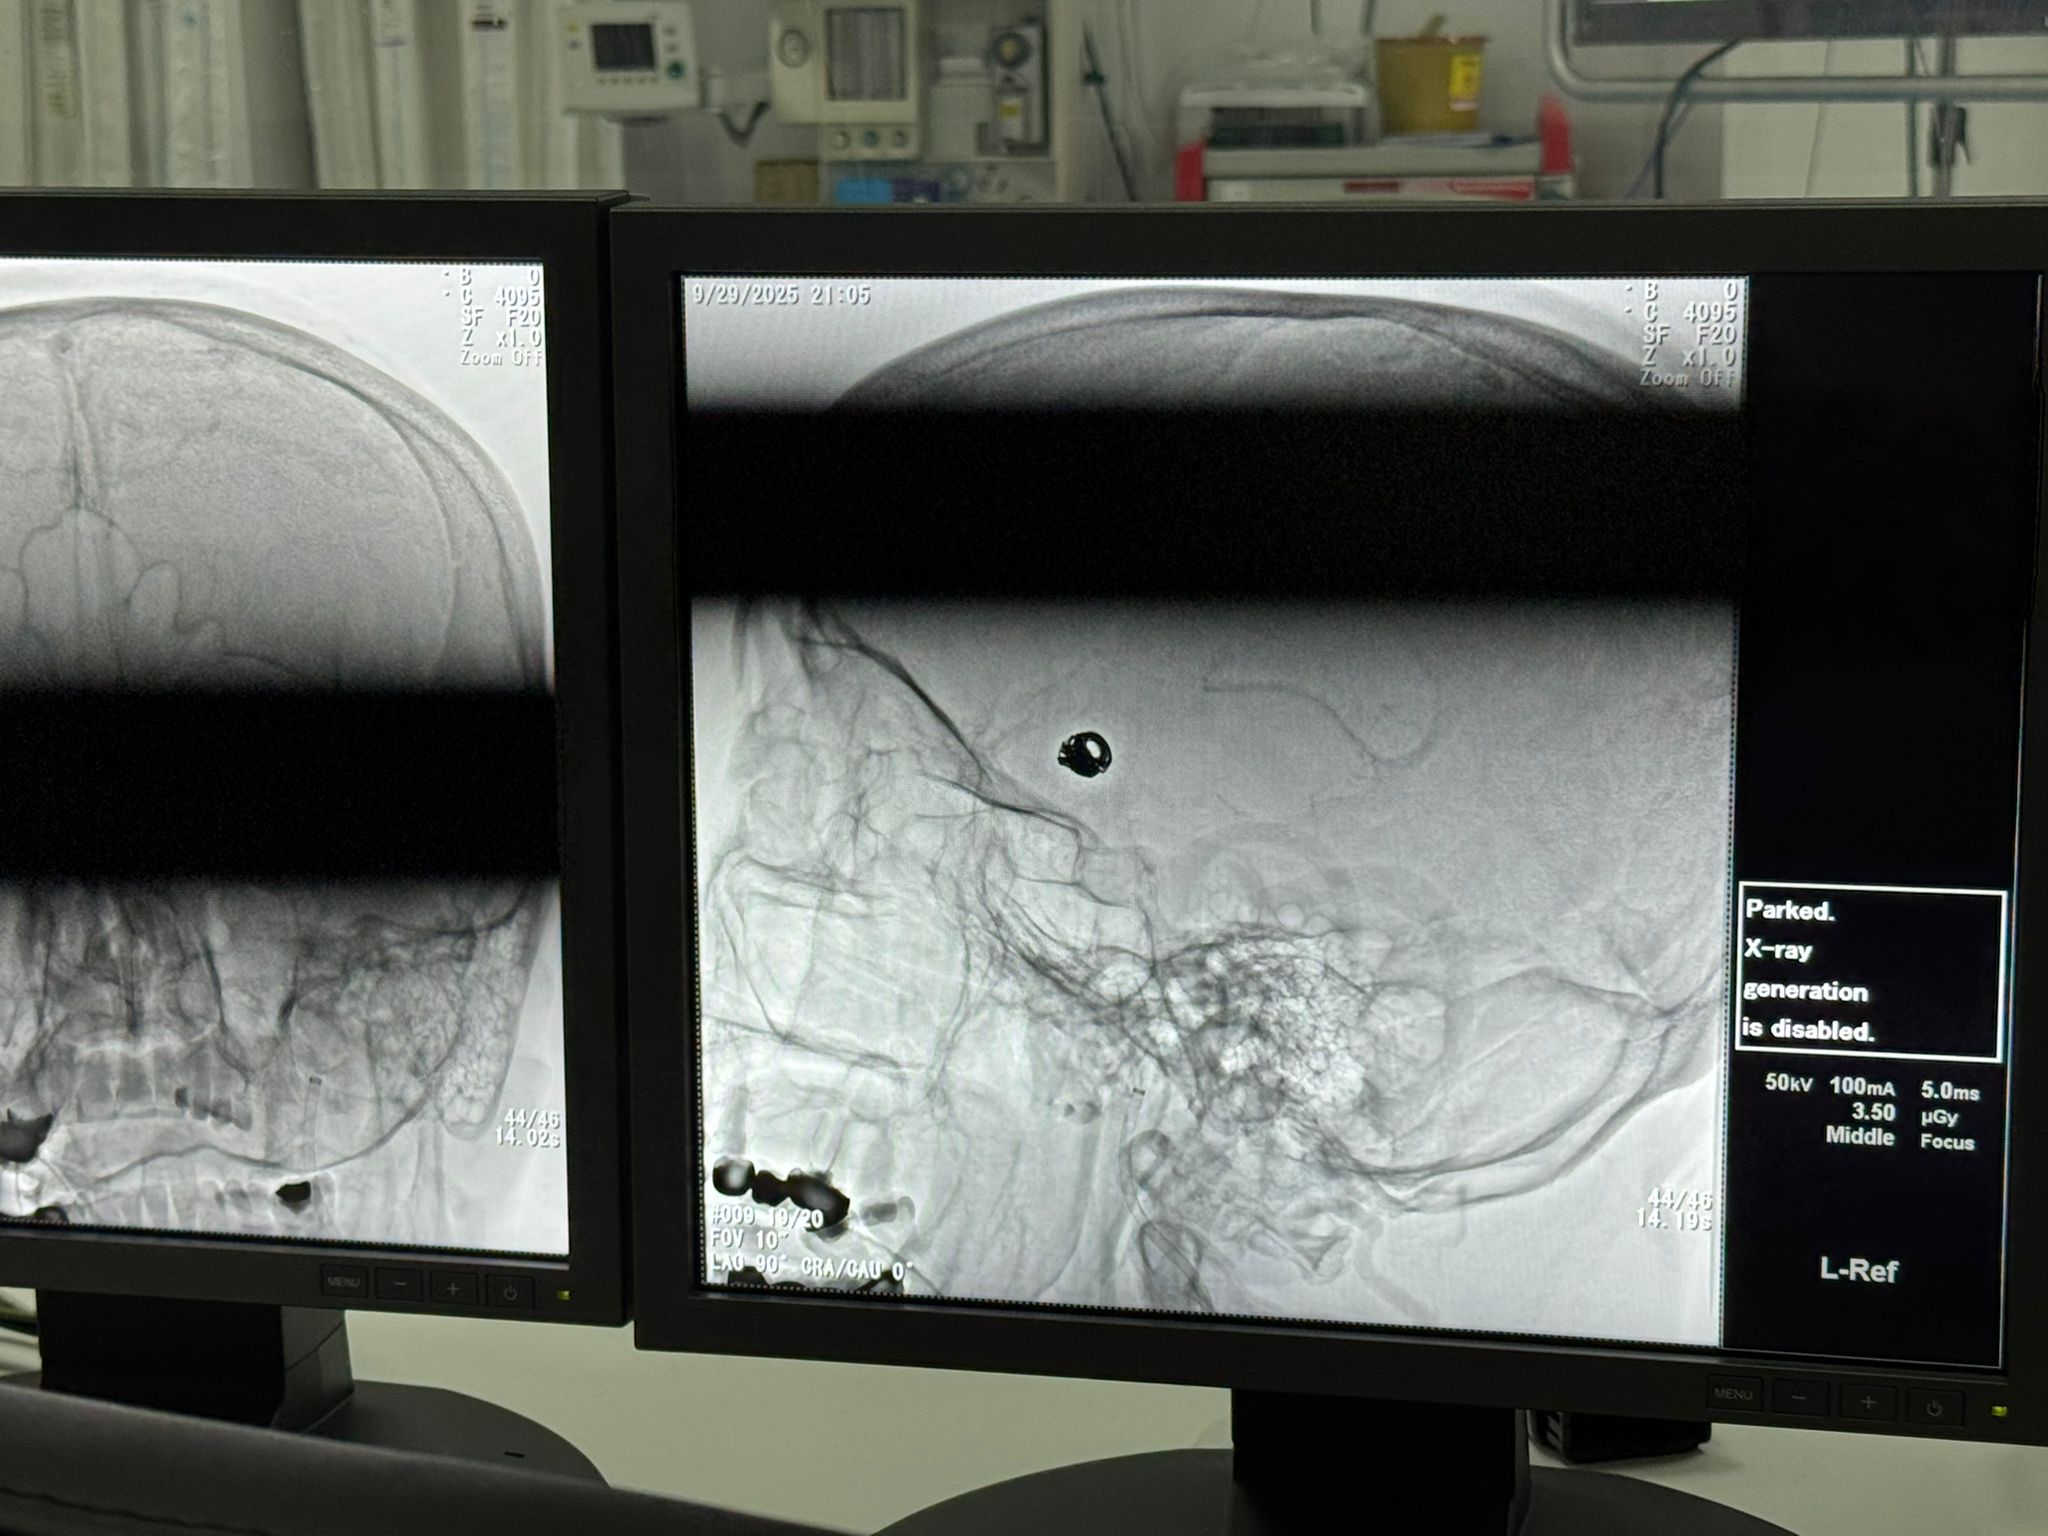

Van Bölge Eğitim ve Araştırma Hastanesi Girişimsel Radyoloji Merkezi'nde bir ilk yaşandı. Beyin damarlarında anevrizma (damar baloncuğu) tespit edilen ve buna bağlı beyin kanaması geçiren 44 yaşındaki hasta, ameliyatsız olarak kapalı yöntemle tedavi edildi.

Radyoloji Uzmanı Berat Demiral, 44 yaşındaki kadın hastanın Bitlis Devlet Hastanesine bilinç durumunda bozulma ve şiddetli baş ağrısı şikayeti ile gittiğini, yapılan tomografi incelemesinde beyin kanamasının saptanmasının üzerine detaylı incelerle birlikte beyin damarlarında bir baloncuğun tespit edildiğini söyledi. Ardından hastanın tedavisi için ambulans ile Van Bölge Eğitim ve Araştırma Hastanesine Sevk edildiğini aktaran Demiral, burada hastanın son teknoloji cihazlarla, kapalı ameliyat yöntemiyle tedavi edildiğini dile getirdi.

Hastanın beyin damarlarındaki baloncuk, anjiografi yöntemiyle girilerek, herhangi bir cerrahi kesi yapılmadan başarıyla kapatıldı. Bu yöntem sayesinde hasta, açık beyin ameliyatı risklerine maruz kalmadan tedavisini sürdürüyor.

Anevrizma tedavisinde iki farklı yöntemin bulunduğunu hatırlatan Demiral, sözlerini şöyle sürdürdü: "İlki bizim uyguladığımız kapalı yöntemdir. Bu yöntemde kasıktan girilerek beyin damarına ulaşılır, baloncuk platin telle kapatılır. İkincisi ise açık beyin ameliyatıdır. Bu yöntemde kafatası açılarak anevrizmanın boynuna klips adı verilen özel bir kıskaç yerleştirilir ve baloncuğun kanla dolması önlenir. Her iki yöntemde de amaç aynıdır; baloncuğu devre dışı bırakmak. Ancak kapalı yöntem, hasta açısından daha konforludur. Açık yara olmadığından komplikasyon riski daha düşüktür ve hastanede kalış süresi daha kısa olup hastalar daha kısa sürede günlük aktivitelerine dönebilmektedir. Hastamızı bir hafta önce işlem için almıştık. Şu anda durumu gayet iyi olup takibi ve ilaç tedavisi devam etmektedir."